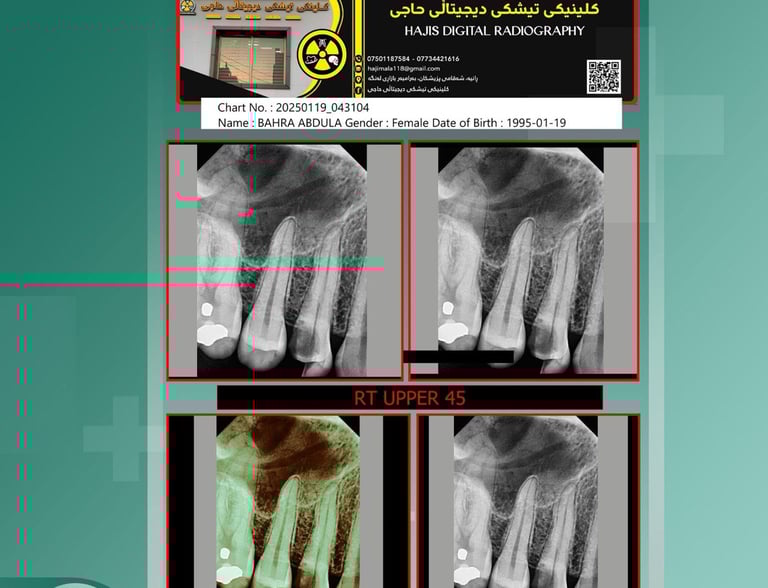

ئێکسڕەی

گرتنی وێنەی ڕوون و ڕاستەقینە بۆ تاقیکردنەوەی تەندروستی.

گاڵێری

وێنەکانی کلینیکی حاجی بە پیشەسازی و تەکنەلۆجیای نوێ